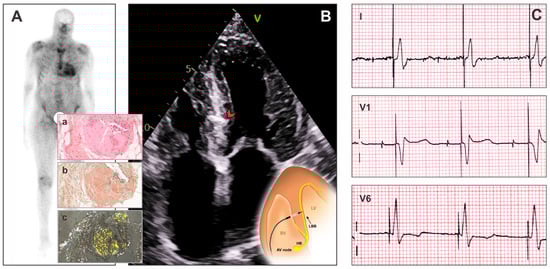

Left Bundle Branch Area Pacing in Transthyretin Cardiac Amyloidosis: A Narrative Review

by Maria Herrera Bethencourt, Arnt V. Kristen, Vincent Algalarrondo, Guram Imnadze and Andreas Müssigbrodt

J. Clin. Med. 2026, 15(1), 305; https://doi.org/10.3390/jcm15010305 - 31 Dec 2025

Background/Objectives: Transthyretin cardiomyopathy (ATTR-CM) is frequently associated with conduction disease requiring pacing. Conventional right ventricular pacing may worsen cardiac function, whereas left bundle branch area pacing (LBBAP) aims to preserve physiological activation. Evidence for LBBAP in ATTR-CM remains limited. Methods: A [...] Read more.

Background/Objectives: Transthyretin cardiomyopathy (ATTR-CM) is frequently associated with conduction disease requiring pacing. Conventional right ventricular pacing may worsen cardiac function, whereas left bundle branch area pacing (LBBAP) aims to preserve physiological activation. Evidence for LBBAP in ATTR-CM remains limited. Methods: A structured narrative review of PubMed and Google Scholar was performed through November 2025 using predefined terms related to LBBAP and ATTR-CM. Peer-reviewed articles, case reports, case series, and relevant abstracts were included. Studies exclusively on light-chain cardiac amyloidosis were excluded. Results: Ten publications met inclusion criteria, comprising three case reports, five case series, one retrospective cohort without a comparator, and one cohort comparing LBBAP with cardiac resynchronization therapy (CRT). In total, 56 patients with ATTR-CM underwent LBBAP. Implantation success was high, with stable acute and mid-term electrical parameters. Follow-up (typically 3–12 months) showed stable electrical parameters with narrow paced QRS complexes and preserved or improved left ventricular ejection fraction in most reports. Symptomatic improvement and reductions in natriuretic peptides were variably described. No major lead-related complications were reported. Comparative data remain sparse and inconclusive. Conclusions: This review suggests that LBBAP is a feasible and safe pacing approach in patients with ATTR-CM and may help to stabilize or improve heart failure symptoms. Further prospective studies are needed to confirm its clinical effectiveness. Full article

Show Figures

Figure 1